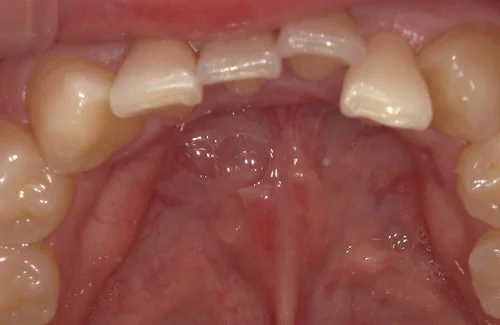

ウィ・スマイルの症例

- 症例1

治療期間 4カ月

治療費 23.1万円(月額1,925円~)

※上顎前歯部、下顎前歯部の叢生をマウスピース型矯正装置で改善したケース。矯正治療上のリスクとして、治療中の虫歯、歯根吸収、歯肉炎 ・歯周炎の発生などが考えられる。